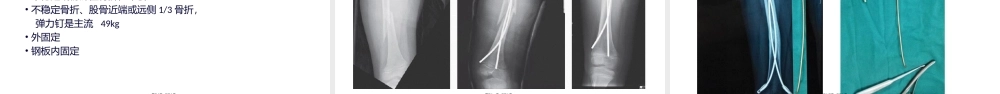

儿童(értóng)股骨干骨折第一页,共三十页。概述(ɡàishù)•发病率:1.6%•男性儿童多见•发病年龄双峰分布,初学走路儿童(单纯跌倒(diēdǎo))和青少年早期(高能量损伤)第二页,共三十页。受伤(shòushāng)机制•跌落(diēluò)伤•重物砸伤•车祸•虐待第三页,共三十页。诊断(zhěnduàn)•明确(míngquè)的受伤机制•大腿的肿胀、畸形,局部疼痛•对于多发伤或头外伤、不能行走或严重肢体功能障碍的患儿,诊断较困难•单纯股骨干骨折,血细胞比容很少低于30%第四页,共三十页。X线表现(biǎoxiàn)•应包括股骨(gǔgǔ)全长、髋关节和膝关节•骨盆正位片•合并股骨转子间骨折、股骨颈骨折或股骨近端骨骺损伤•也可合并膝关节骨骺损伤、胫骨骨折•排除病理性骨折第五页,共三十页。第六页,共三十页。分型•横行(héngxíng)、螺旋形、短斜形•粉碎性或非粉碎性•闭合性骨折或开放性骨折•大部分为单纯的横行、闭合性、非粉碎性骨折第七页,共三十页。骨折部位(bùwèi)不同移位形式不同第八页,共三十页。治疗(zhìliáo)•年龄因素•受伤机制•患儿体重•损伤(sǔnshāng)类型•骨折类型第九页,共三十页。新生儿至6个月•骨膜较厚和骨骼重塑能力较强,很好需要严格的复位和外固定•单纯应用(yìngyòng)Pavlic吊带或夹板固定•可接受的复位标准为:内外翻成角<30°,前后成角<30°,旋转移位<10°,短缩<2cm•如果不能满足此复位标准需要行髋人字石膏固定•极少使用牵引第十页,共三十页。第十一页,共三十页。第十二页,共三十页。第十三页,共三十页。学龄前儿童(értóng)6个月-5岁•短缩在2cm以内的单纯股骨骨折,早期人字石膏固定•低能量损伤造成的骨折,应用行走人字石膏•短缩大于2cm,或者明显不稳定(wěndìng),3-10皮肤牵引或骨牵引•外固定•弹力钉•钢板内固定第十四页,共三十页。第十五页,共三十页。注意事项•屈髋90°,外展30°,膝关节屈曲60°有利于维持下肢长度及骨折复位•石膏外翻塑形•腘窝处棉垫保护,防止腘窝血管受压•下肢外旋15°固定•X线摄片,确保(quèbǎo)骨折复位•24小时内密切观察末梢血运情况,预防骨筋膜室综合症第十六页,共三十页。第十七页,共三十页。第十八页,共三十页。行走(xíngzǒu)人字石膏第十九页,共三十页。5-11岁患儿•较多的治疗方法•无移位或轻度(qīnɡdù)移位,人字形石膏固定•不稳定或粉碎性骨折,牵引•不稳定骨折、股骨近端或远侧1/3骨折,弹力钉是主流49kg...